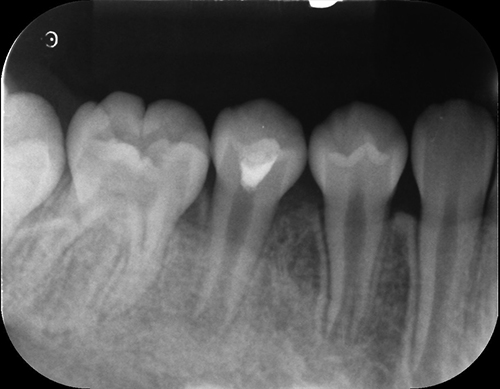

【初期】

【中期】

【完了】

初期:膿が陰になっている

中期:膿が除去できているが歯根が短い

完了:膿もなく歯根もしっかり伸びている